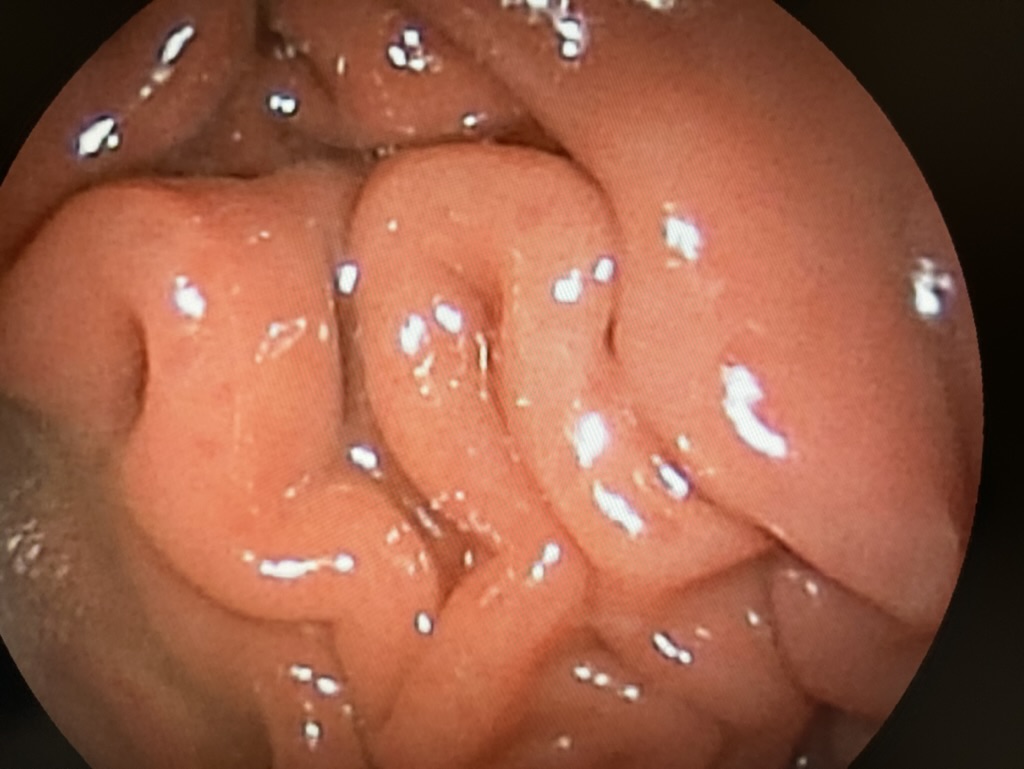

Beroende på dessa undersökningar och behandlingssvar kan det bli tal om vävnadsprover som vanligen görs med endoskopi under narkos.